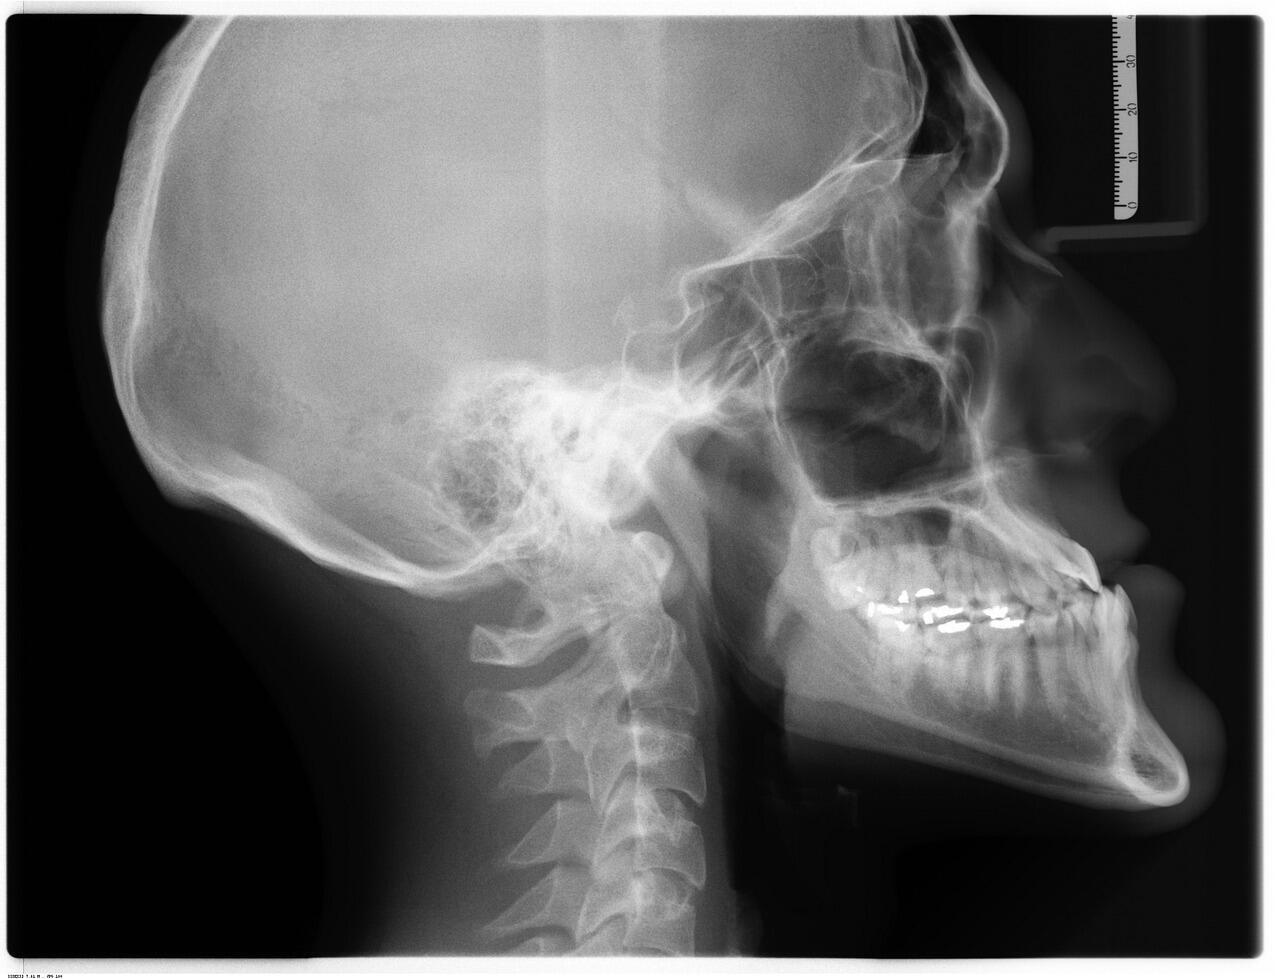

Digital X-Rays & Imaging

ceramic-braces-2

Low-radiation digital X-rays reveal what's hidden beneath the surface — early decay, bone loss, infections, and more

Why X-rays are essential

Many dental problems are invisible to the naked eye. Decay between teeth, infections at the root tip, bone loss around teeth, and even cysts can all develop silently without symptoms. Digital X-rays allow us to detect these issues early — when treatment is simpler, less invasive, and more affordable. Our digital X-ray system uses up to 90% less radiation than traditional film X-rays.

Types of X-rays we use

Depending on what's needed, we may take small intraoral X-rays that show individual teeth in detail, or a panoramic X-ray (OPG) that shows your entire jaw, all teeth, sinuses, and jaw joints in a single image. For complex cases, we also have access to 3D CBCT scanning, which provides detailed three-dimensional views essential for implant planning, wisdom tooth assessment, and complex root canal cases.